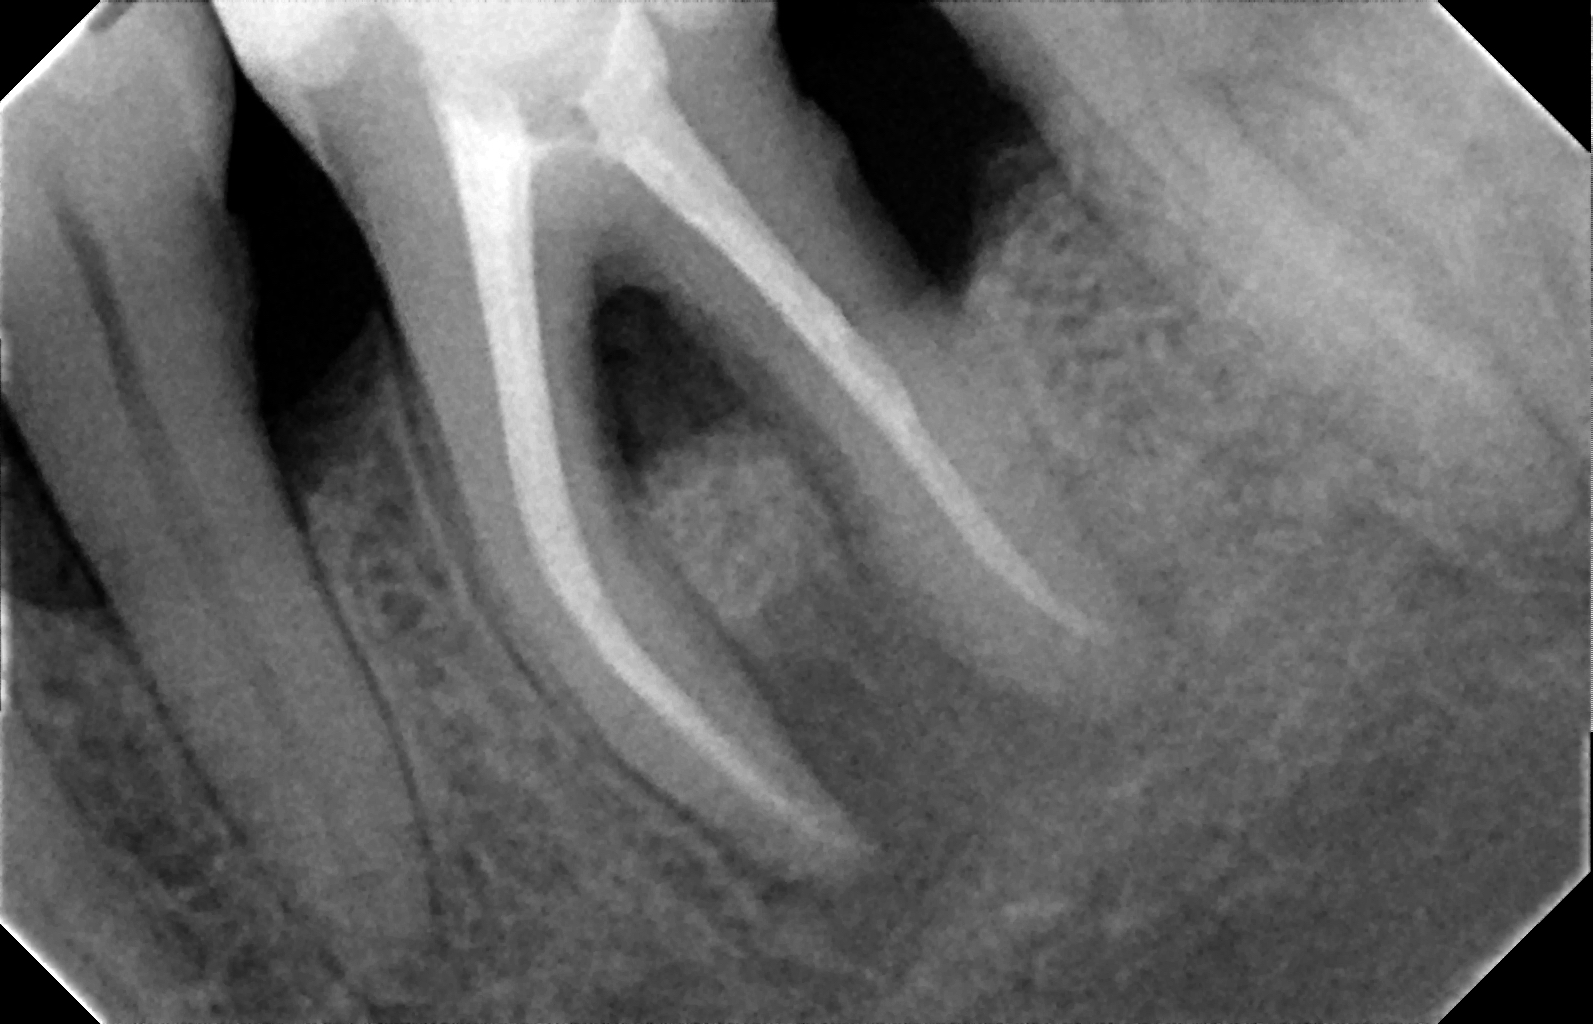

Retratamiento de conducto

El retratamiento de conducto implica limpiar nuevamente los conductos dentales, debido a que se generó un proceso infeccioso interno producto de una obturación defectuosa, fractura o filtración, de esta forma se evita dolor, inflamación o pérdida de la pieza dental afectada.